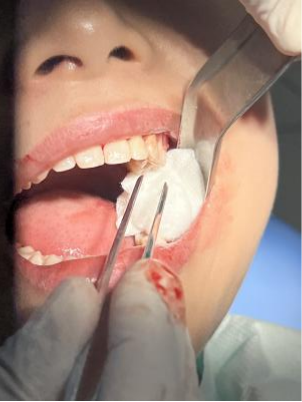

智齿拔除步骤

口腔检查- 拍片-局麻-检查麻醉效果- 切开牙龈 - 去除邻牙阻力、骨阻力和根阻力 - 取出牙冠及牙根- 拔牙创搔刮复位- 进行缝合—咬棉球止血 。